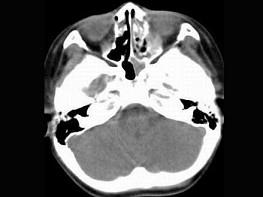

问题 男,7岁,无意发现鼻腔肿物,无明显症状,CT如图所示,最可能诊断为 ( )

选项 A、鼻乳头状瘤 B、鼻炎及副鼻窦粘膜下囊肿 C、鼻炎 D、鼻炎鼻息肉 E、鼻淋巴瘤

答案 D